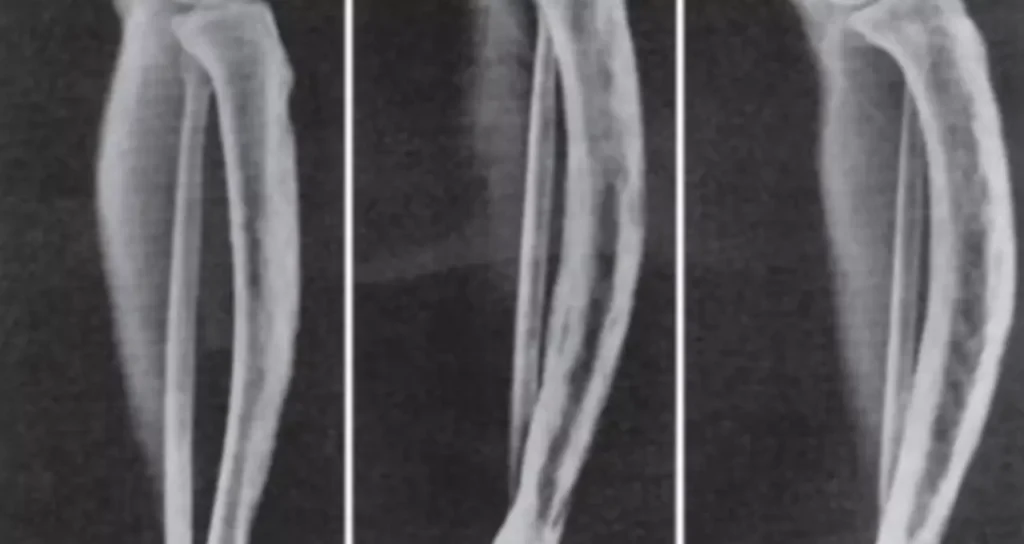

O primeiro passo é obter um diagnóstico médico detalhado, geralmente feito por meio de exames como radiografias, cintilografia óssea, tomografia computadorizada e exames laboratoriais que medem os níveis de fosfatase alcalina no sangue.